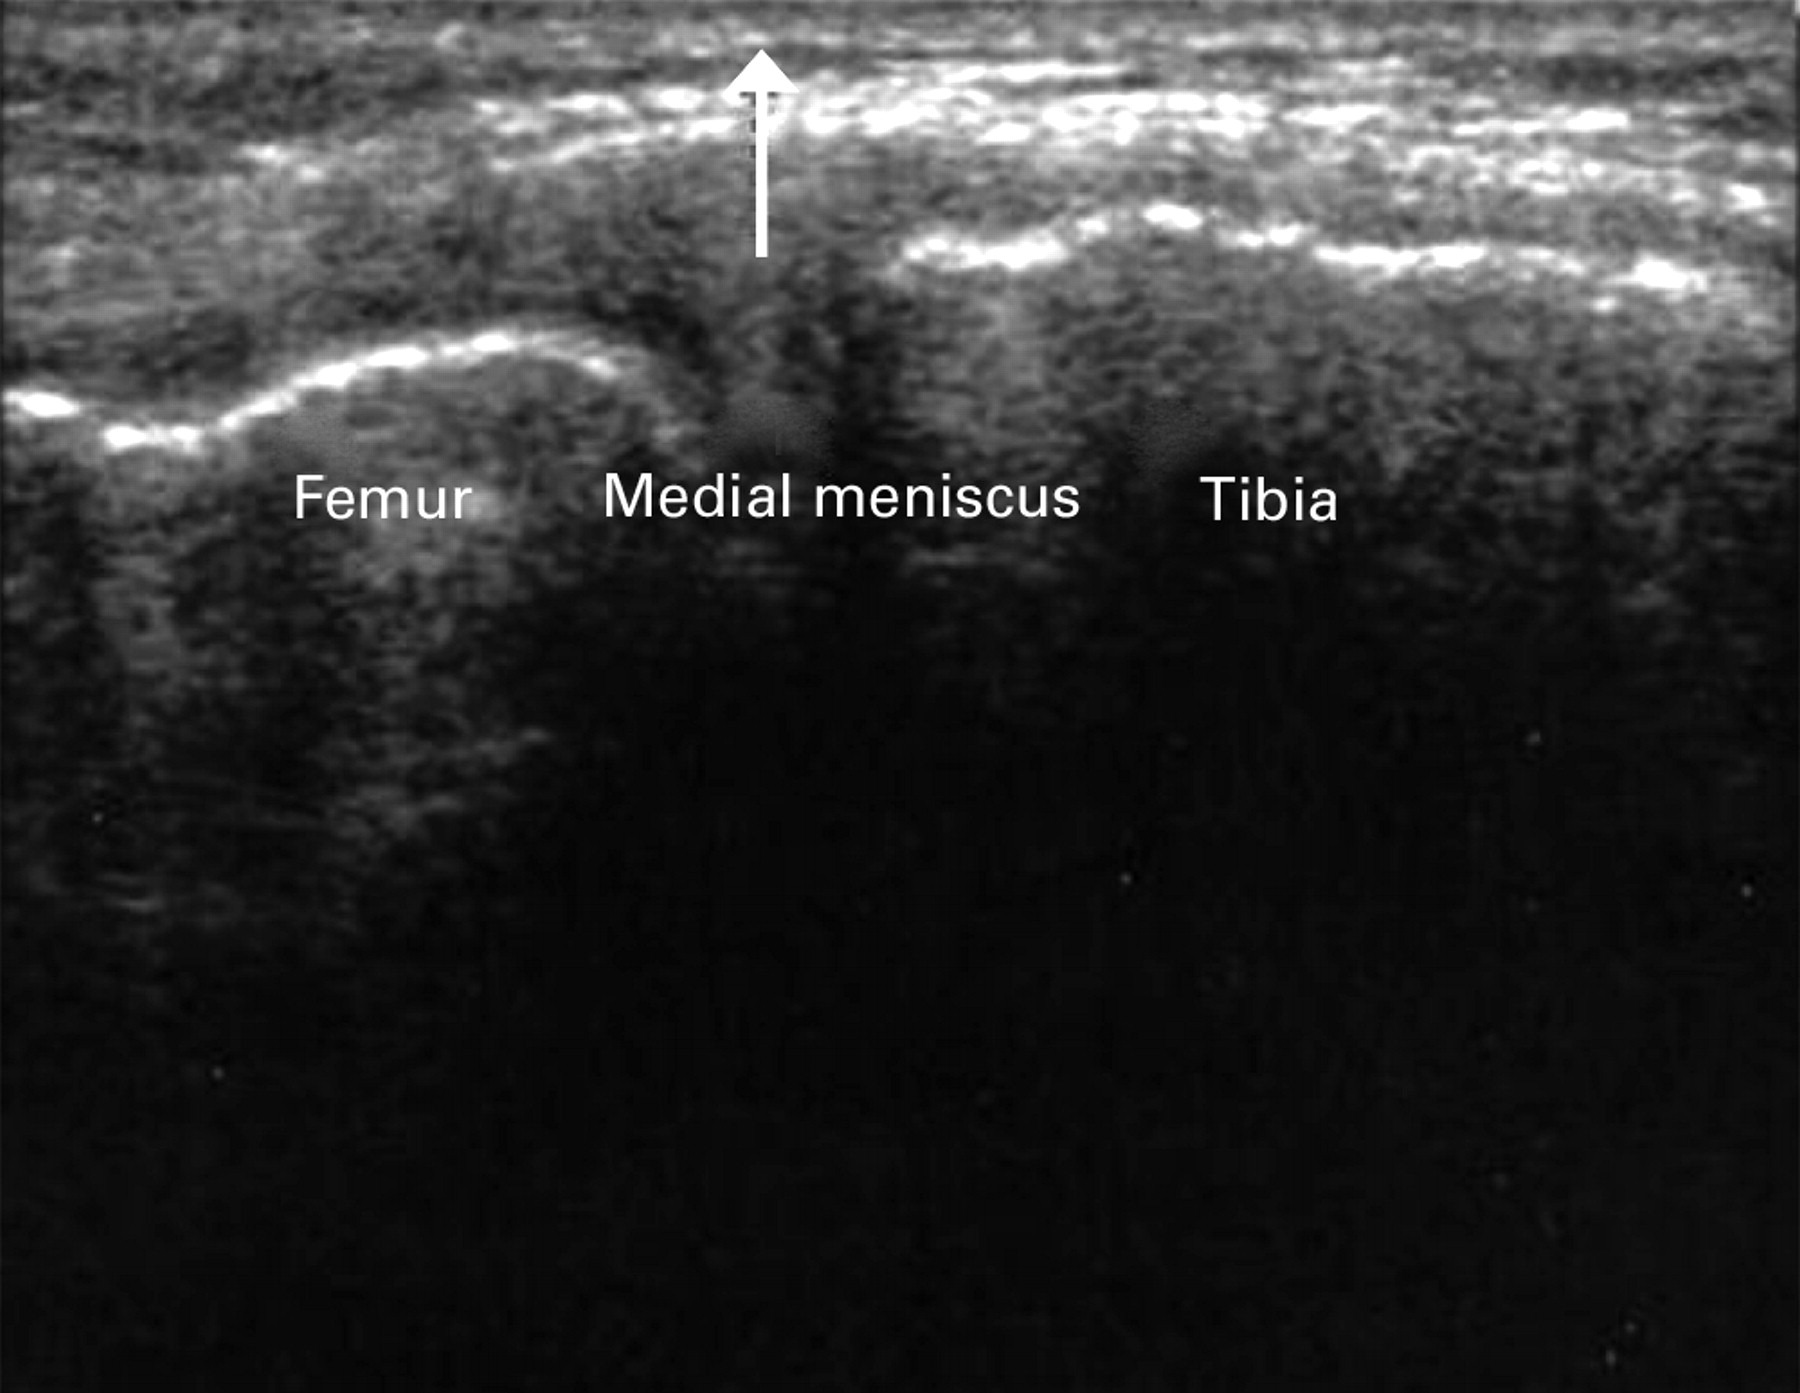

1/Có vết rách là sự hiện diện của vùng giảm âm trong chính sụn khớp liên quan tới mặt khớp , lưu ý ảnh giả hay sót chỗ đứt khe khoeo bằng cách so sánh với đầu gối bên không có triệu chứng